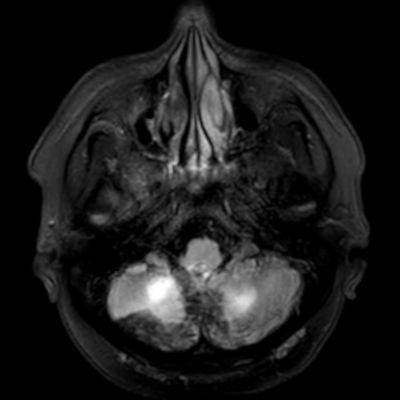

45 yaş, K

4 yıl önce akut sağ hemiparezi, konuşma bozukluğu ve dış merkezde serebellar iskemi tanısı ile ASA kullanımı öyküsü

Konuşma bozukluğu, yersiz gülme ve ağlama atakları, denge kaybı ve uyuşmaları devam ediyor

CADASIL